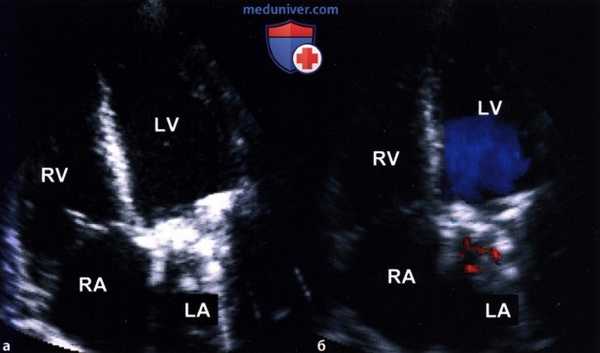

Механический протез митрального клапана. Акустическая тень, отбрасываемая клапанным протезом, мешает при сканировании сердца из апикальной позиции датчика исследованию левого предсердия - как структурных его особенностей, так и гемодинамических феноменов:

а - Двумерная ЭхоКГ.

б - Цветовое допплеровское картирование.

3. Выбор ультразвукового окна. Трудности, вызываемые отбрасыванием акустической тени клапанным протезом, можно в какой-то степени обойти за счет выбора оптимального ультразвукового «окна». Так, при механическом протезе митрального клапана как сканирование, так и допплеровское исследование левого предсердия из апикальной позиции почти невозможно, в то время как, располагая датчик парастернально, можно значительно улучшить «видимость».